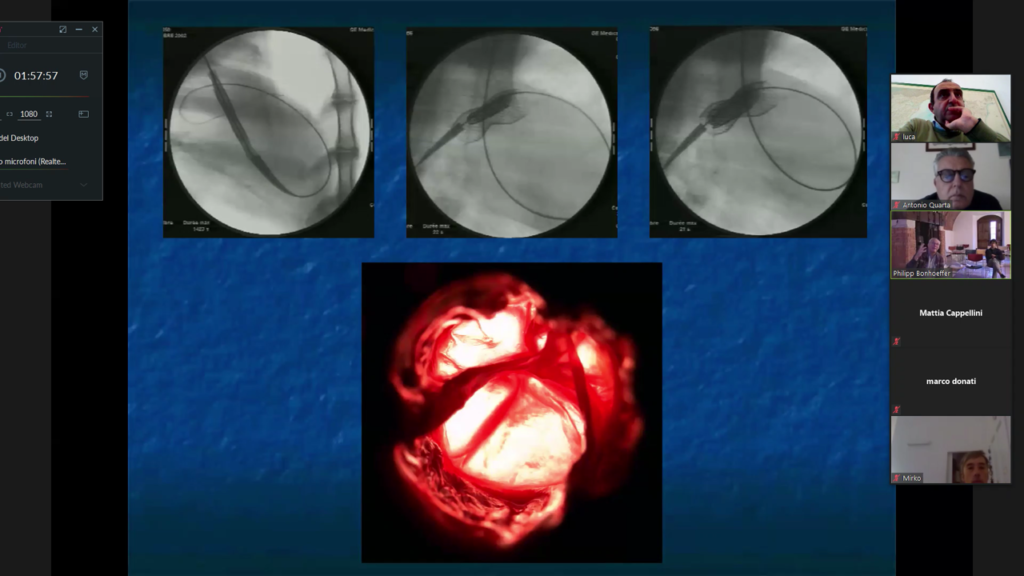

Negli anni mette a punto altre tecniche interventistiche tra le quali la rivoluzionaria procedura non invasiva che permette di inserire una valvola ricavata dalla giugulare bovina nell’arteria polmonare senza ricorrere all’intervento chirurgico a cuore aperto (valvola Melody).

Il dott. Bonhoeffer ha fatto ben capire l’importanza della multidisciplinarità ponendo particolarmente attenzione ai materiali e alle tecnologie; in particolare ha illustrando la parte di modellazione 3D, l’analisi ad elementi finiti ed in ultimo la realizzazione delle parti mediante la stampante 3D, tecnologie che oggi ragazzi hanno a disposizione anche a scuola ma che lui aveva iniziato ad utilizzare già nel 2004 con il team specialistico formato prevalentemente da ingegneri.

La ricerca infatti non finisce mai, ed in collaborazione con una équipe multidisciplinare, composta da di cardiologi, radiologi, cardiochirurghi, ingegneri biomedici ed una ditta, ha sviluppato e progettato una seconda generazione di valvola che ha permesso di trattare un maggior numero di pazienti.